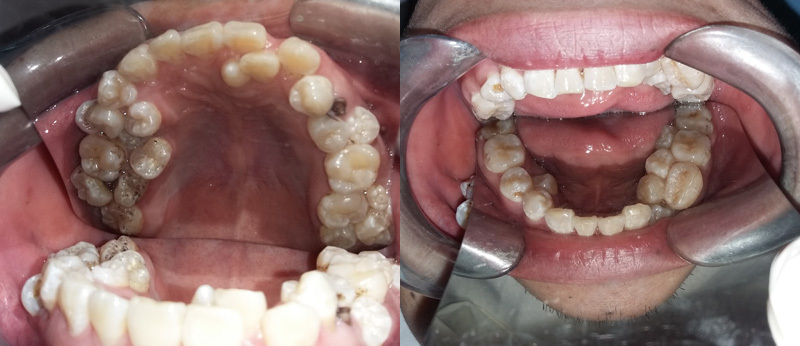

13 chiếc răng mọc chen chúc trên 2 hàm của bệnh nhân |

Tại đây các bác sĩ đã hết sức bất ngờ khi phát hiện ngoài chiếc răng sâu, bệnh nhân bị mọc thừa đến 13 chiếc răng ở vị trí răng 4 và 5 trên 2 hàm.

Các răng mọc lệch, chen chúc, dàn hàng ngang khiến việc vệ sinh khó khăn, gây sâu, viêm tủy.